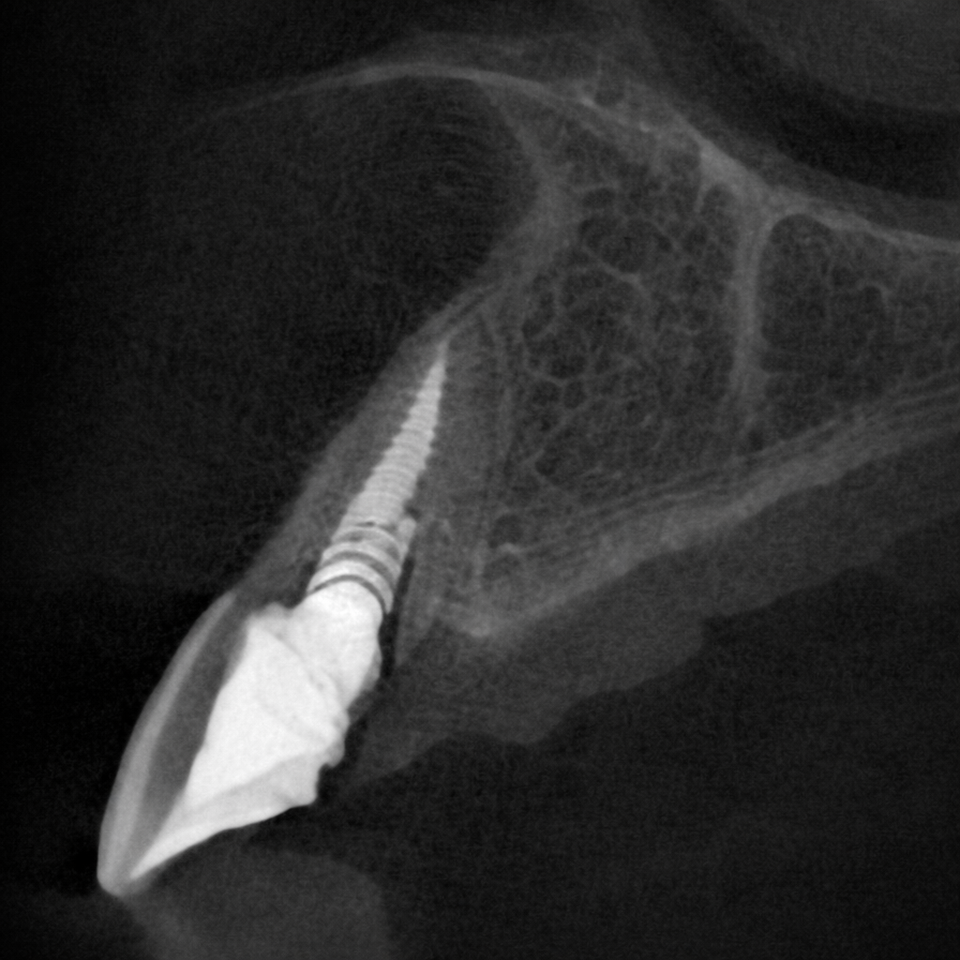

We also treated a patient who presented with significant gum recession affecting the right central tooth. Due to the severity of the condition, extraction was necessary.

Our team carefully planned and executed the placement of an implant-supported crown, focusing on achieving optimal gum symmetry, natural contours, and long-term function.

The final outcome restored not only the patient’s smile but also their confidence.